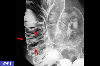

Two cases of MALT lymphoma in the large intestine.

X-ray